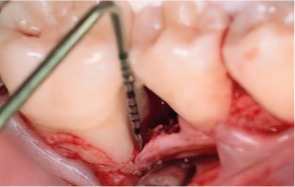

STEP 02

Scaling Root Planning을 실시

-

STEP 03

치석 및 치태 등 제거

STEP 04

엠도게인 도포